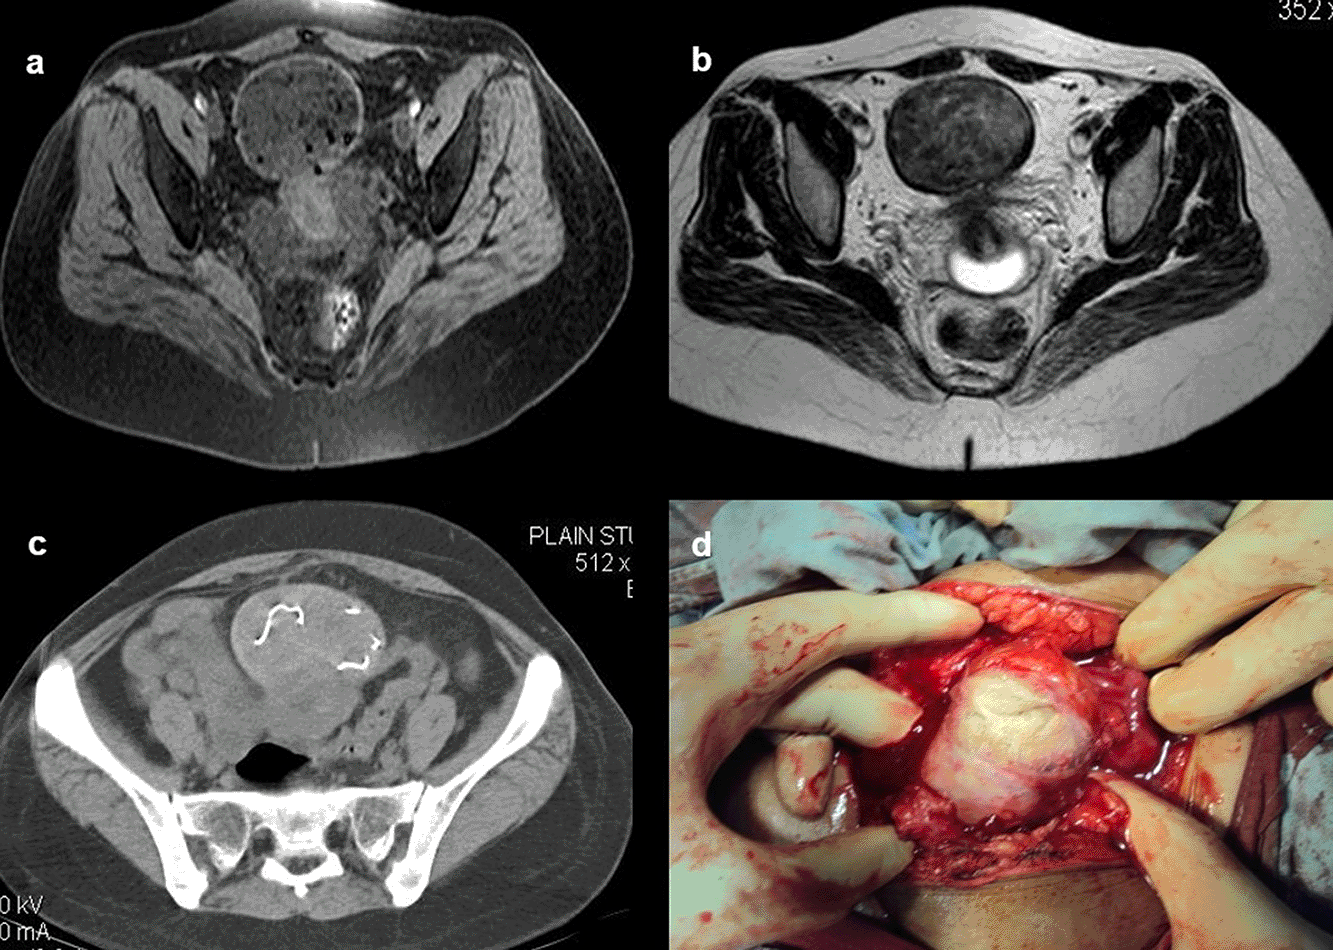

Case 10: A 33-year-old female came with a history of bleeding pervaginal for six months. MRI shows heterogeneous altered signal intensity soft tissue mass anterior to the uterus with multiple hypointense foci within. CT showed multiple linear metallic strings within a mass of soft tissue density anterior to the uterus, suggesting a foreign body (gossypiboma). The patient was operated on, and a large surgical sponge was removed.

After surgery, not infrequently, patients have surgical items inside their bodies. Surgical drains, wound gauze packs, bandages, skin staples, small surgical staples, intra-arterial, intravenous, intra-spinal, and intraabdominal catheters are among the postoperative supplies that are most frequently seen. Other uncommon materials, such as retained abdominal sponges (Figure 10a-d) and needles, that were unintentionally left behind after surgery, are challenging to find clinically and radiographically because patients have vague symptoms, these objects are difficult to see on radiographs, and the radiologist and referring physician have a low level of suspicion for such objects. The nursing staff may perform a comprehensive sponge count at the conclusion of a surgical procedure and identify any remaining surgical sponges right away. A misplaced sponge may not be identified for months or even years after surgery if it is not found at that time. The foreign body reaction to a surgical sponge left inside the body for a long time is frequently called a gossypiboma. The sponge’s cotton matrix is what creates the foreign body reaction’s nidus. There is the development of a foreign body granuloma with surrounding fibrosis and retraction around the cotton nidus. Many people have no symptoms, and the retained sponge is often only unintentionally found when the patient has a radiological examination for another reason.13–17